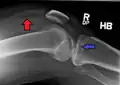

Fractures of the tibial plateau are caused by a varus (inwardly angulating) or valgus (outwardly angulating) force combined with axial loading or weight bearing on knee. The classically described situation in which this occurs is from a car striking a pedestrian's fixed knee (bumper fracture). A bumper fracture is usually a fracture of the lateral tibial plateau, caused by a forced valgus movement. This causes the lateral part of the distal femur and the lateral tibial plateau to come into contact, compressing the tibial plateau and causing the tibia to fracture. The name of the injury is because it was described as being caused by the impact of a car bumper on the lateral side of the knee while the foot is planted on the ground, although this mechanism is only seen in about 25% of tibial plateau fractures.[5] The term "bumper fracture" was coined in 1929 by Cotton and Berg.[6] Fracture of the neck of the fibula may also be found, and associated injury to the medial collateral ligament or cruciate ligaments occurs in about 10% of cases.[7][8]

However, most of these fractures occur from motor vehicle accidents or falls. Injury can be due to a fall from height in which knee forced into valgus or varus. The tibial condyle is crushed or split by the opposing femoral condyle, which remains intact. The knee anatomy provides insight into predicting why certain fracture patterns occur more often than others. The medial plateau is larger and significantly stronger than the lateral plateau. Also, there is a natural valgus or outward angulation alignment to the limb which coupled with the often valgus or outwardly angulating force on impact will injure the lateral side. This explains how 60% of plateau fractures involve the lateral plateau, 15% medial plateau, 25% bicondylar lesions. Partial or complete ligamentous ruptures occur in 15-45%, meniscal lesions in about 5-37% of all tibial plateau fractures.[9]

In all injuries to the tibial plateau radiographs (commonly called x-rays) are imperative. Computed tomography scans are not always necessary but are sometimes critical for evaluating degree of fracture and determining a treatment plan that would not be possible with plain radiographs.[10] Magnetic Resonance images are the diagnostic modality of choice when meniscal, ligamentous and soft tissue injuries are suspected.[11][12] CT angiography should be considered if there is alteration of the distal pulses or concern about arterial injury.